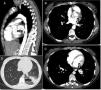

Chest computed tomography and angiography with sagittal (A) and axial (B) reconstructions showing: A (arrow) – an abnormal artery from the thoracic aorta to supply the left lower lobe of the lung; B (arrow) – the left inferior pulmonary vein receiving the drainage from the lobe defining an intralobar sequestration; C (arrow) – both the aberrant artery branch (#) and the inferior pulmonary vein (*) parallel to each other; D (arrow) – a heterogeneous density of the pulmonary parenchyma surrounded by ground glass opacity corresponding to the affected left lower lobe of the lung.

She was admitted for aetiological investigation. Pulmonary sequestration was suspected and an early chest computed tomography and angiography was performed without need for further investigation since it revealed an intralobar pulmonary sequestration, with arterial supply from a thoracic aortic branch (Fig. 1) and venous drainage into pulmonary veins. Her respiratory function tests were normal.

Our case represents the most common presentation of pulmonary sequestration: intralobar, on the LLL with arterial supply from the descending thoracic aorta and venous drainage into the pulmonary veins.2